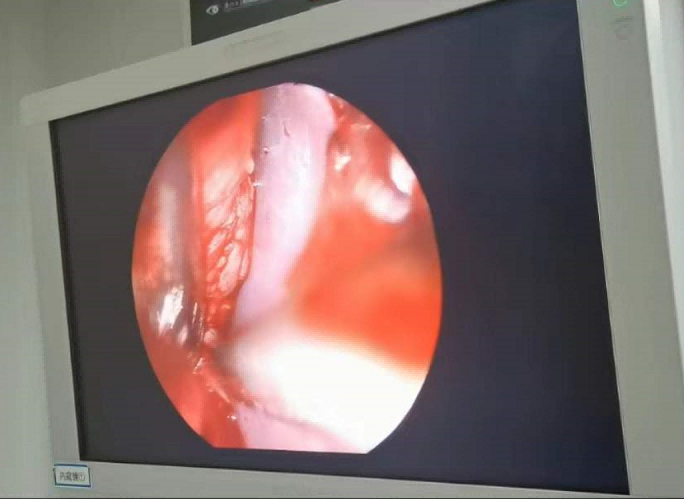

送到廈門眼科中心的時候,林老師受傷的左眼還在流血。眼整形科的鄧?yán)っ鞲敝魅吾t(yī)師緊急為他安排了“內(nèi)鏡下眶骨折修補+鈦網(wǎng)鈦釘植入術(shù)”。

圖為:內(nèi)鏡下眼眶骨折修補術(shù)

手術(shù)過程中林老師還出現(xiàn)了驚險的眼球后大出血,還好鄧?yán)っ饔诰o急之中穩(wěn)住了病情,并順利完成了手術(shù)。術(shù)后第二天,林老師的術(shù)后反應(yīng)就很輕,恢復(fù)良好,他一邊感謝著鄧?yán)っ鞯?ldquo;救命之恩”,一邊自嘲著自己示范了個“反面教材”。